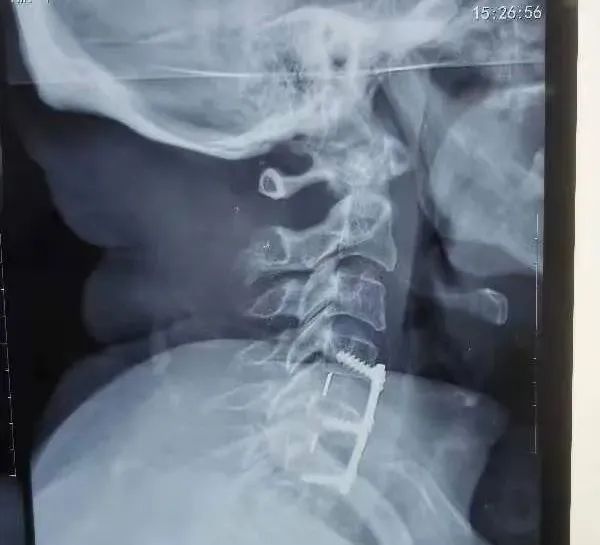

入院查各项化验、检查无手术禁忌,于2022年4月1日在全麻下行颈4-5、5-6椎间盘切除、植骨融合内固定术。

术后第三天复查颈椎正侧位片钉棒位置良好,佩戴颈托下地活动。自诉症状明显减轻,双手麻木基本消失,双下肢活动自如,感觉已基本正常。